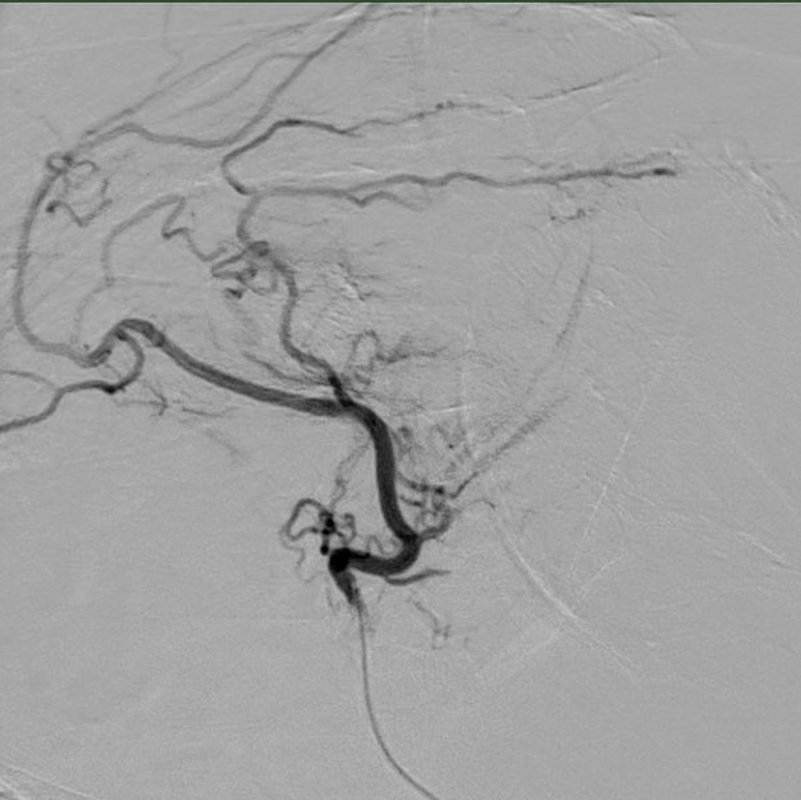

Nach sorgfältiger lokaler Betäubung wird minimalinvasiv über ein Gefäß in der Leiste ein weniger als zwei Millimeter dünner Katheter bis in die winzigen Seitenäste der Gelenkarterien vorgeschoben. Mittels Einschwemmung kleiner Kügelchen („Mikrosphären“) können diese Seitenäste anschließend teilweise verschlossen („embolisiert“) werden. Die Blutversorgung des Gelenkes insgesamt wird hiervon nicht beeinflusst. Lediglich die überschießende Durchblutung wird ganz lokal reduziert.